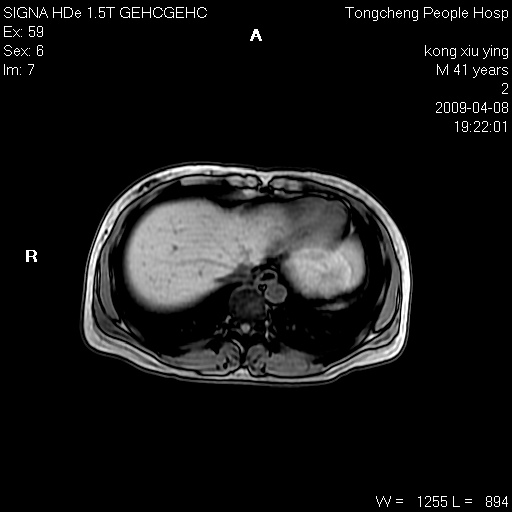

标题: CL1008:【经典】胆囊石榴籽样结石。

女,41岁。健康体检——彩超提示:胆囊显示不清。平素健康,无不适感。

腹部mr扫描及mrcp,图像如下: